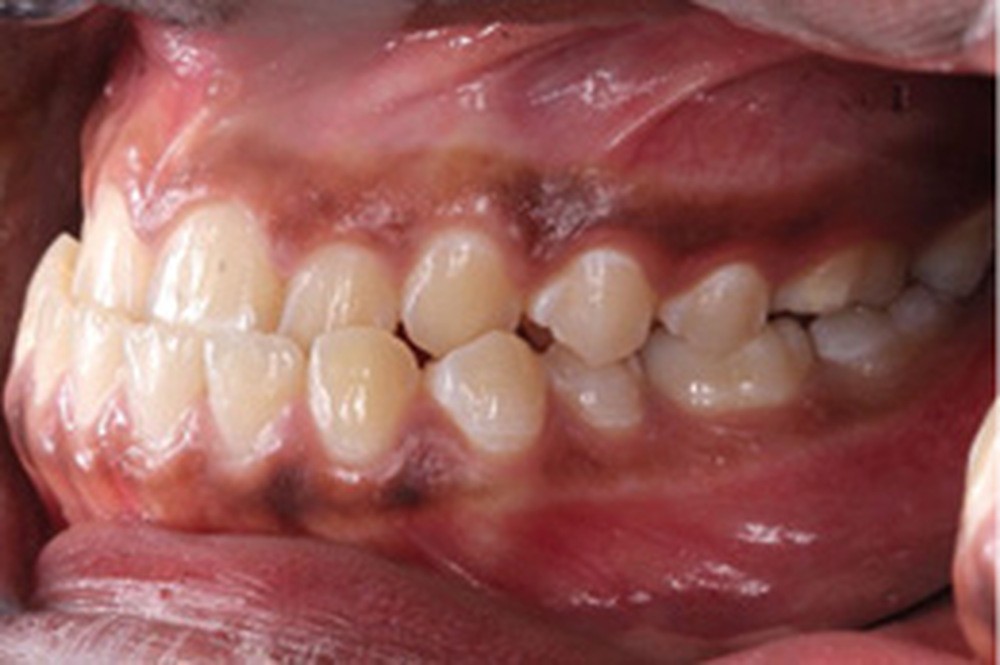

L’arcade maxillaire est en V et la voûte palatine profonde. L’arcade mandibulaire a une forme en U (non-concordance des formes d’arcade) et présente des malpositions des dents cuspidées. La médiane mandibulaire est décalée à gauche de 2 mm ; le recouvrement antérieur est de 2 mm ; les molaires sont en classe III avec un surplomb inversé.

Lors de la réévaluation post-chirurgicale, l’examen exo-buccal montre peu de changement, excepté l’occlusion et l’harmonie labiales retrouvées. Le surplomb et le recouvrement sont normalisés et le brossage amélioré. Les formes d’arcade sont concordantes, les médianes inter-incisives recentrées et les molaires et canines en classe I.